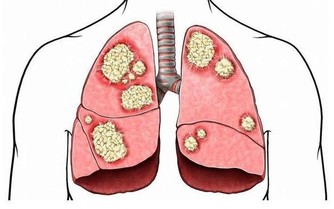

*****3、冠心病*****

根據數據顯示,近年冠心病的年輕趨勢越來越明顯。但是由於早期冠狀動脈粥樣硬化的症狀不明顯,常常會被人所忽視。

殊不知,如若冠狀動脈粥樣斑塊破裂,發生心肌缺血,就會引發致死性心律失常,最終導致猝死。

那這類猝死到底有啥先兆呢?以下幾個症狀,需要警惕,及時去醫院治療:

①憋悶、心悸、眩暈;

②胸前區壓榨性疼痛、肋骨下疼痛、左胸部疼痛;

③出冷汗和失神等;